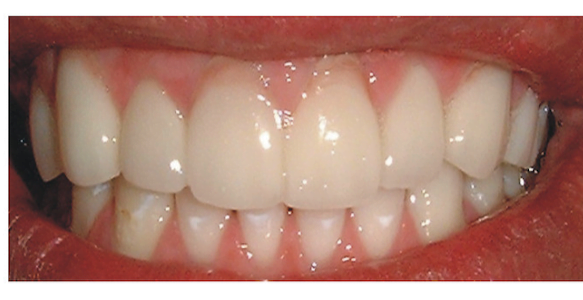

He did not like the repeat fillings and also thought his teeth were too long or misshapen. We discussed Emax veneers as a better long term option. Veneers are known to lats over 20 years+ if looked after.

2 weeks later new porcelain Emax veneers were bonded to the teeth. You may notice some pink porcelain at the gum levels; we use this when there has been gum recession and the patient does not want extremely long teeth.

The Emax will not stain as composites do and will rarely chip or fail. The occlusion is always investigated for any irregularities beforehand.